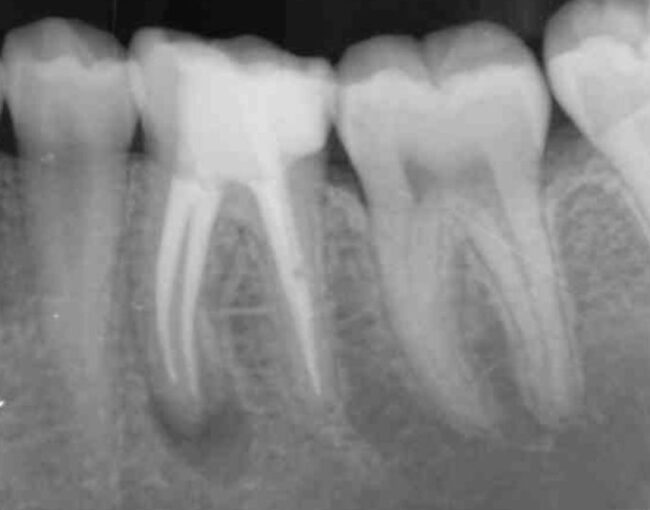

Organizado por O2O Endo Academy, los doctores Francisco de la Torre y Rafael Cisneros han sido los encargados de impartir este curso teórico-práctico en el que se han dado todas las claves para una endodoncia paso a paso.